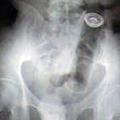

Razvada Samo pokažite mu to fotografijo ... Šokantna rentgenska fotografija izpahnjene stegnenice, posledica nespametnega početja.